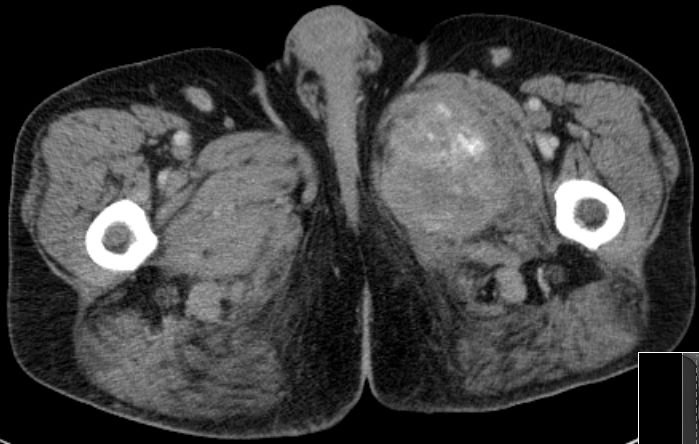

| Knochenmetastasen | 61-jähriger Patient, der vor 2,5 Jahren ein primär hepatisch metastasiertes Rektumkarzinom hatte.

9 Monate FOLFIRI/Erbitux ergaben eine CR der Lebermetastasen.

Mit verschiedenen systemischen und chirurgischen Maßnahmen Tumorkontrolle bis jetzt.

Nun Schmerzen in der linken Leiste besonders beim Treppensteigen.

Das CT zeigt eine Schambeinmetastase mit großem Weichteiltumor.![]() |

Der Weichteiltumor ragt nach caudal in den Adduktorenkanal.![]() |

Cranial ist das symphysennahe Schambein völlig zerstört.![]() |